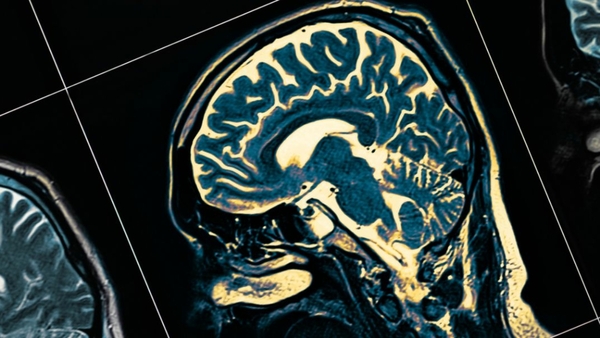

Un grupo de investigadores del Hospital General de Massachusetts desarrolló un modelo de inteligencia artificial capaz de identificar con más del 90% de precisión a personas que padecen Alzheimer, una enfermedad que deteriora la memoria y otras funciones del cerebro de manera progresiva a lo largo de los años. El equipo, liderado por el doctor Matthew Leming, creó un sistema llamado MUCRAN (Multi-Confound ...[Leer más]